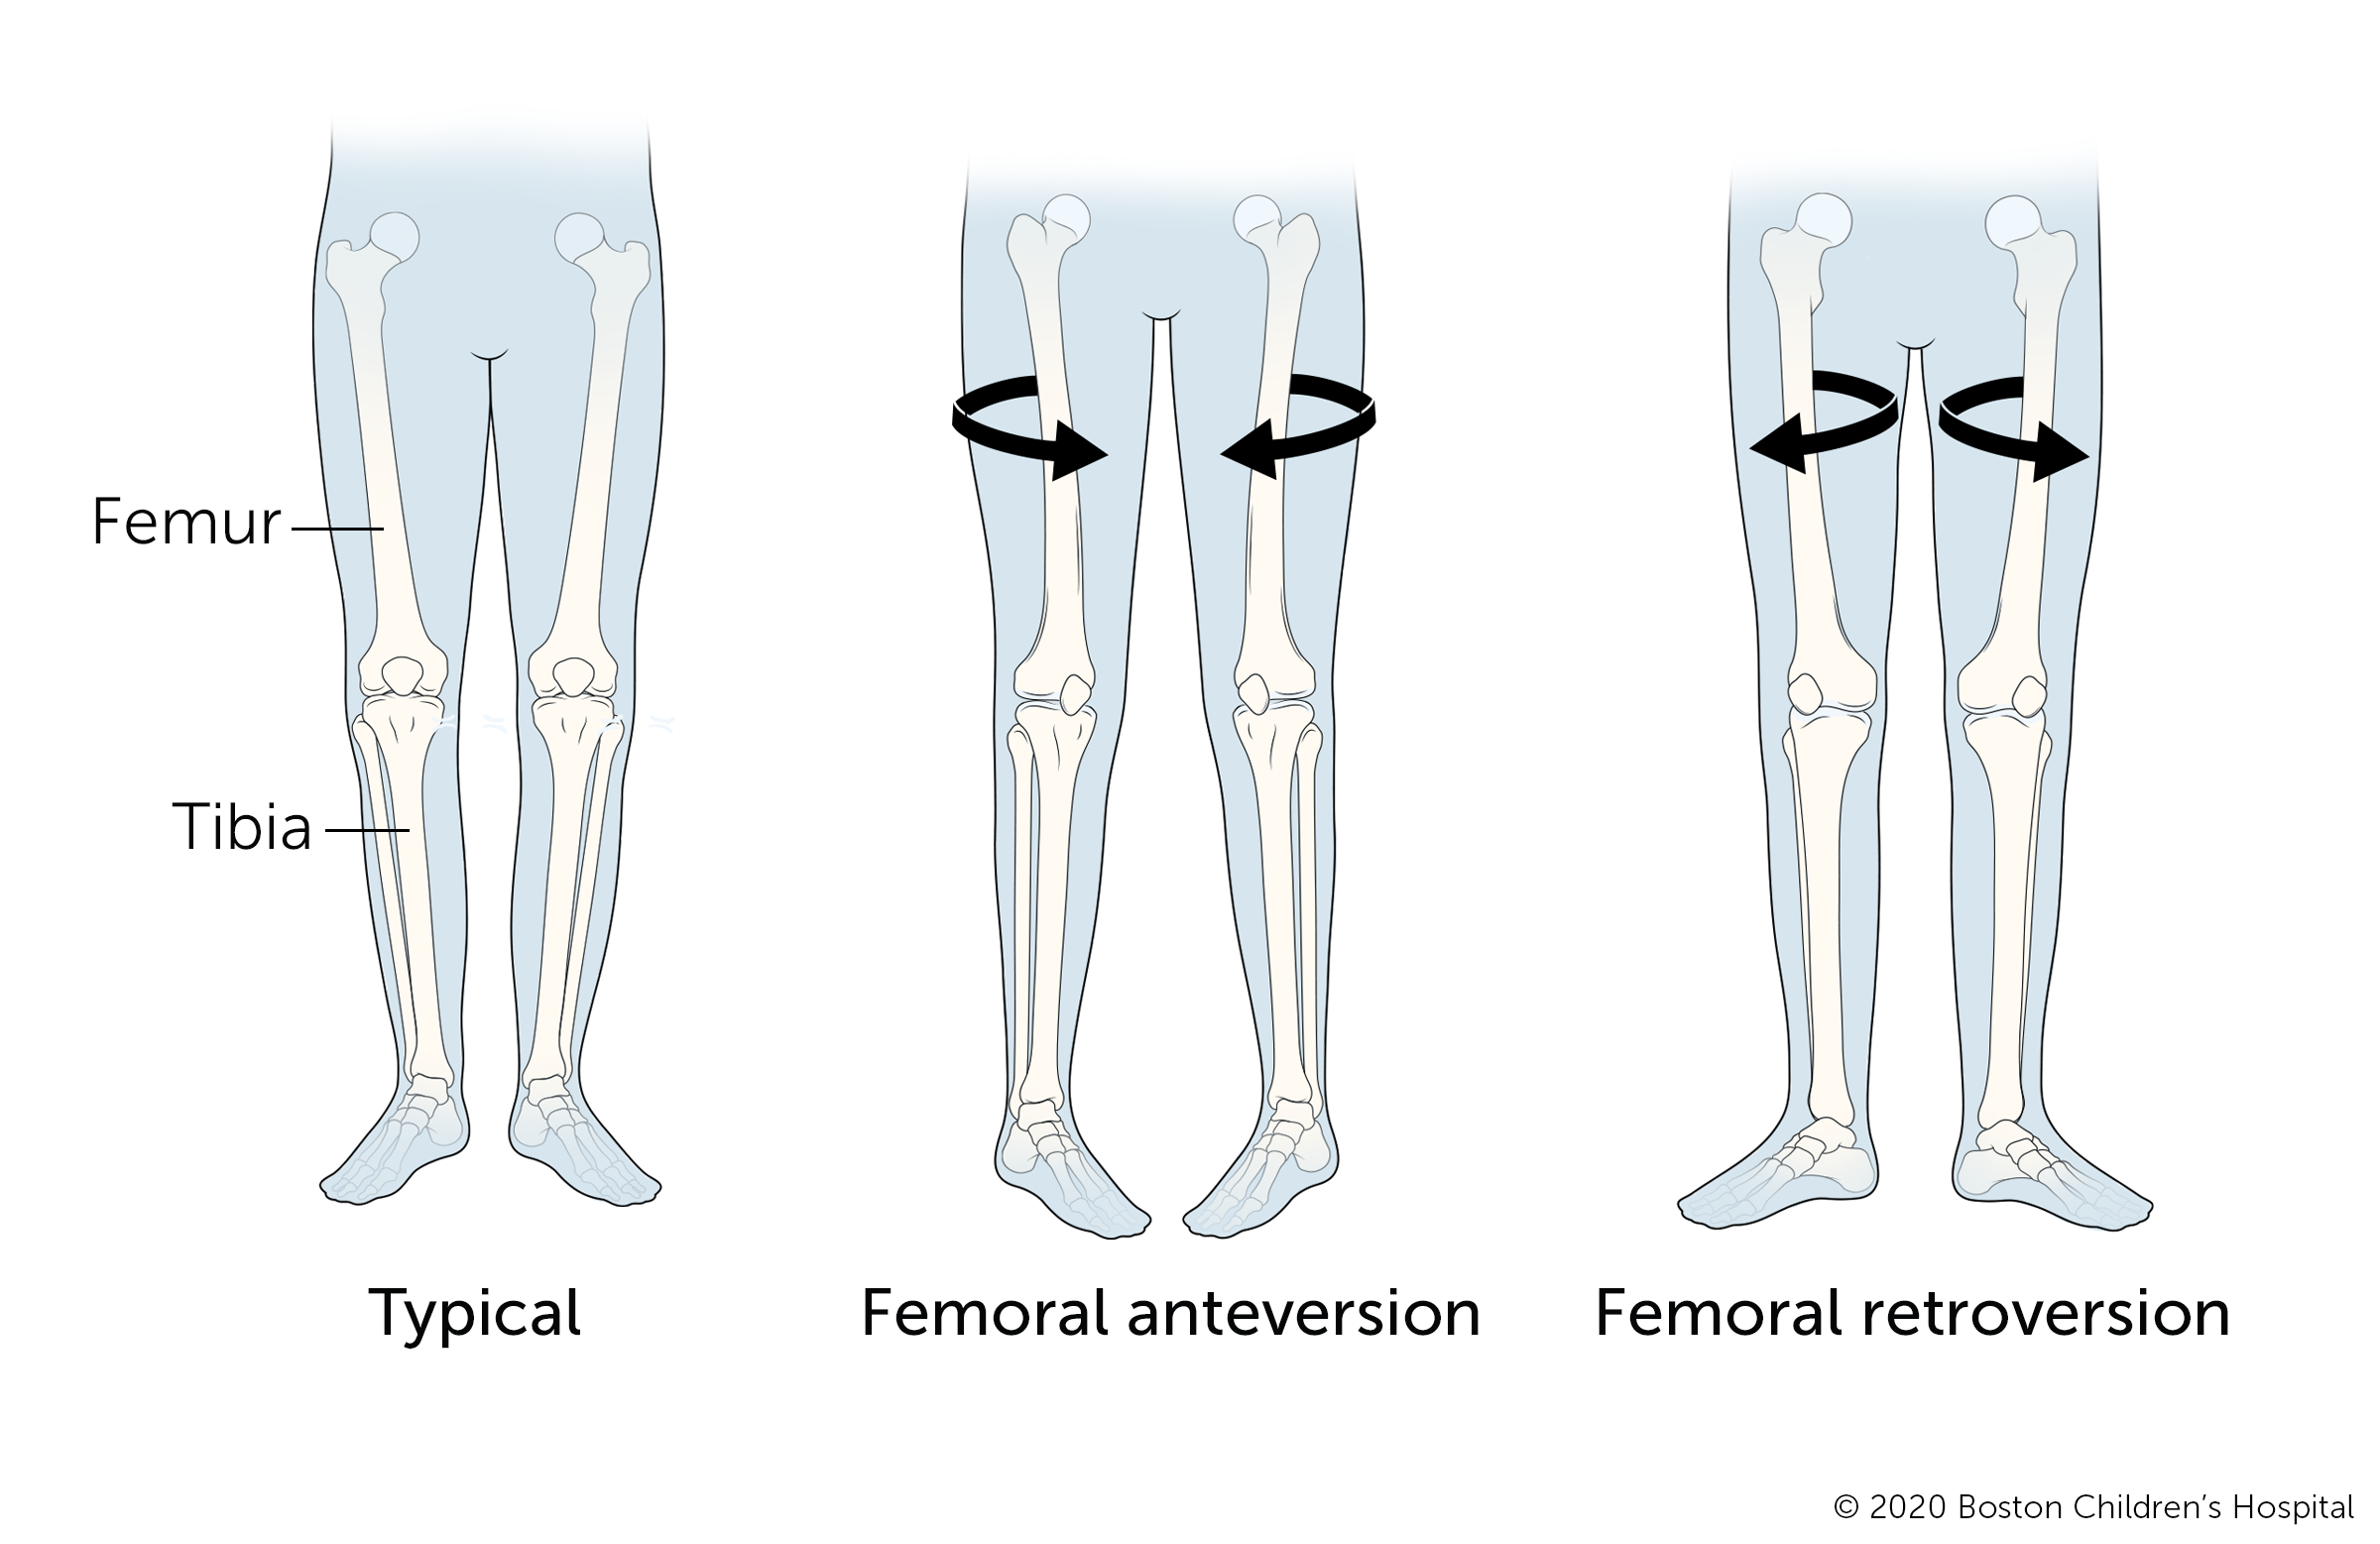

Femoral version

Femoral version describes a child’s upper leg bone (femur) that twists inward or outward. Inward twisting of the femur (femoral anteversion) causes the feet to point inward. Signs of femoral anteversion usually first become noticeable when a child is between 2 to 4 years old, a time when inward rotation from the hip tends to increase. The condition usually gets better without treatment.

Outward twisting of the femur is called femoral retroversion and causes the feet to point outward. It is less common than femoral anteversion. In some cases, femoral retroversion may delay a child’s walking, however, the condition often gets better without medical intervention.

Doctors consider surgery for femoral anteversion or femoral retroversion only if a child is older than 9 and has a very severe condition that causes a lot of tripping and an unsightly gait.